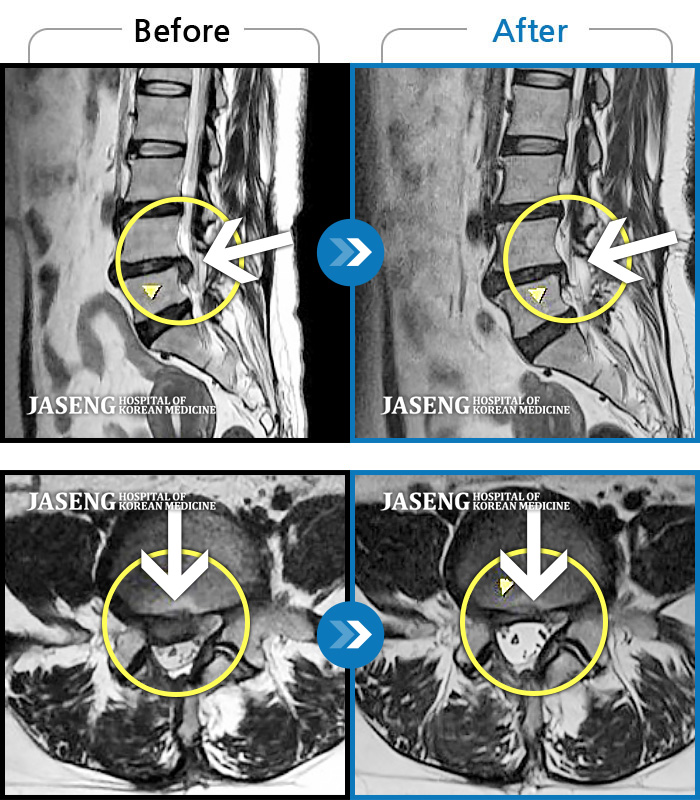

Before

After

우측 허리 뻐근한 통증, 우측 허벅지부터 발목까지 이어지는 당김

2023.03.07 ~ 2023.12.23